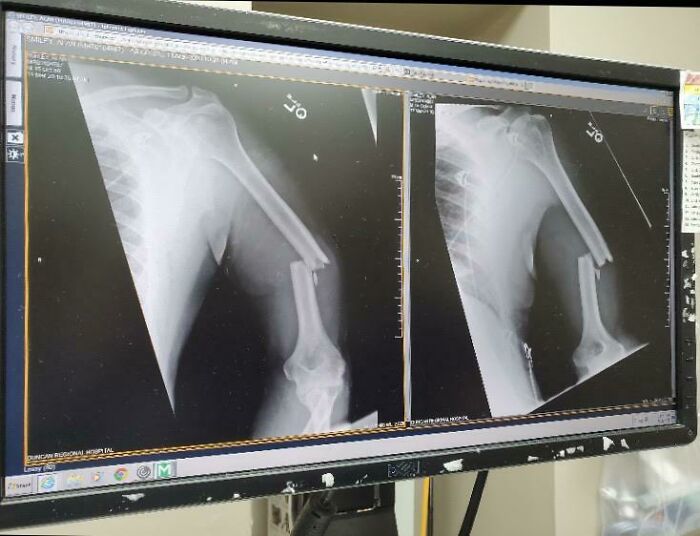

16 Year Old Boy Survived After Being Implanted In The Head By A Fishing Spear